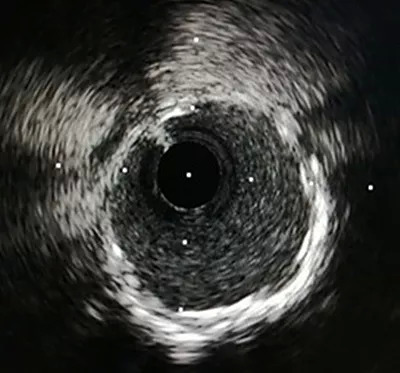

近段支架扩张充分、贴壁良好